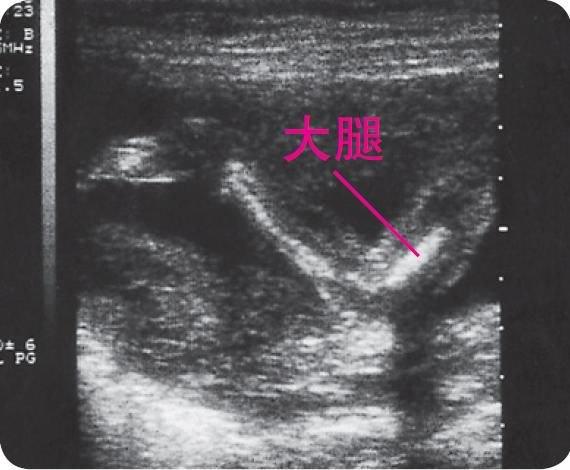

宝宝这时的成长可以说是“日新月异”,到了20周的时候,宝宝就差不多有350克了。这时的宝宝“动手动脚”地和妈妈交流,敲打着城堡的墙壁,他喜欢妈妈立刻做出的反映——用手温柔地抚摸宝宝突袭过的地方。从超声波图上来看,20几周的宝宝面部轮廓已经很清晰了,如果拿宝宝出生后的照片来比较的话,就会发现这面相早早地就“显露峥嵘”了。到了24周的时候,宝宝虽然体重见长,有一斤重了,但还是个“骨感美人”,没有配备任何脂肪储备。